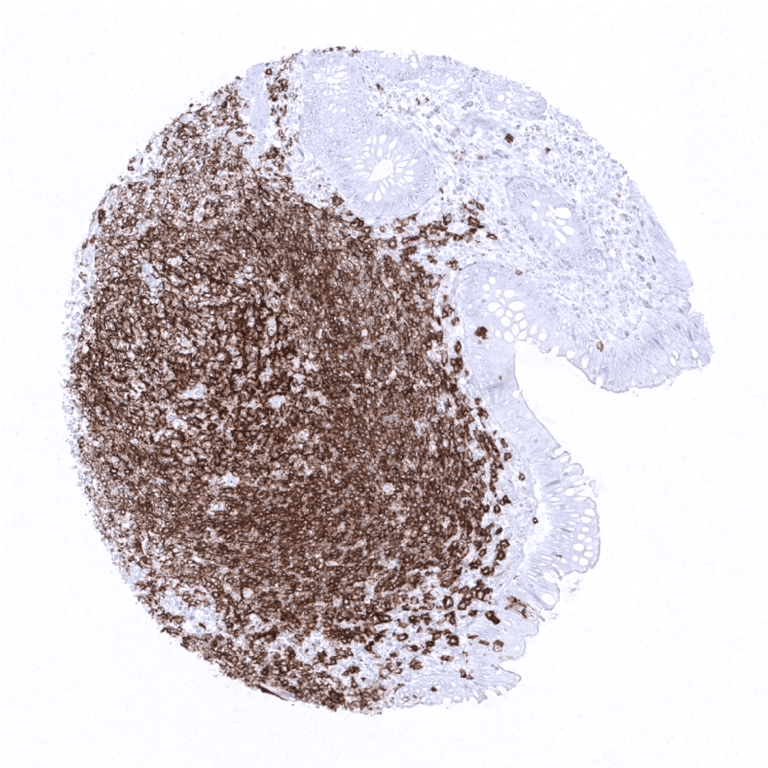

Positive control = Tonsil or appendix: A strong, predominantly membranous staining of the mantle zone B-cells, the germinal centre B- cells and the interfollicular B-cells is required, while all other cells should stain negative.

CD20 is expressed on the vast majority of B-lymphocytes (but not on plasma cells). CD20 positive cells are thus preferably seen in lymphatic organs especially in germinal follicles and mantle zones but some scattered positive lymphocytes can be found in virtually every organ.

Suggested positive tissue control: Tonsil or appendix: A strong, predominantly membranous staining of the mantle zone B-cells, the germinal centre B- cells and the interfollicular B-cells is required, while all other cells should stain negative.

CD20 is expressed in neoplastic cells of most mature B-cell lymphomas but CD20 staining is negative in most B-cell neoplasms derived from immature precursor cells and in plasmocytoma. CD20 is also expressed in neoplastic cells of 80% of nodular lymphocyte predominant Hodgkin lymphoma and in 20% of classic Hodgkin lymphoma. Occasionally, CD20 is aberrantly expressed in T-cell lymphomas. In all other tumor types, variable fractions of CD20 positive B-lymphocytes are detectable as a component of the tumor’s microenvironment.